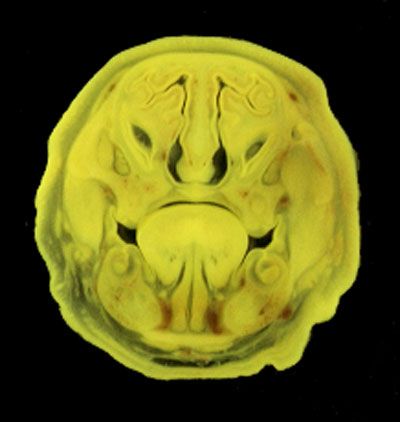

The images below show the normal appearance of Bouin's fluid fixed head sections in specimens at Day 21 of gestation (day mating observed = Day 0).

It is essential that both sides of each section is examined so that structures that exist is several sections can be visualised by the examiner in 3D.

Learning objective: Compare the diagrams with your own specimens and identify all of the structures that have been labelled.

Unlabelled Images